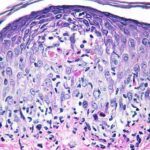

Histopathology. EM is considered the prototype of the vacuolar form of interface dermatitis . The early changes include vacuolization of the basal cell layer; tagging of lymphocytes along the dermal-epidermal junction; and a sparse, superficial, perivascular lymphoid infiltrate . Necrosis of individual keratinocytes in the basal unit occurs, which is the hallmark of EM. Because of its acute nature, there is an orthokeratotic stratum corneum. Mild spongiosis, papillary dermal edema, and extravasation of red blood cells are seen. As the lesion becomes more developed, there is a moderate lichenoid infiltrate of Iymphohistiocytes at the dermal-epidermal junction with exocytosis. More apoptotic keratinocytes within and above the basal epidermal layer are present. The |

intensity of epidermal necrosis varies from vacuolated individual keratinocytes surrounded by lymphocytes (satellite cell necrosis) at the basal unit to confluent necrosis in association with intraepidermal and subepidermal vesicles. The dermal infiltrate comprises lymphocytes and histiocytes. Eosinophils may also be present. Although one study has noted a significant number of eosinophils in drug-induced EM, this has not been noted by others. In the authors’ estimation, a generous number of eosinophils exclude EM. One study has found that an acrosyringium concentration of apoptotic keratinocytes in EM is a clue to a drug etiology . In early lesions of SJSITEN, apoptotic keratinocytes are observed scattered in the basal layer of the epidermis. In established lesions, there are numerous necrotic keratinocytes, even full-thickness epidermal necrosis, and a subepidermal bulla. The dermal inflammatory infiltrate is sparser in TEN than in EM (Fig. 9-278). Extravasated erythrocytes are commonly found within the blister cavity. Melanophages within the papillary dermis occur in late lesions. Eccrine epithelium shows a variety of changes from basal cell apoptosis to necrosis of the duct. |

In general, EM shows less epidermal necrosis, more dermal inflammation, and exocytosis, whereas SJS and TEN reveal more epidermal necrosis, less dermal inflammation, and exocytosis. However, due to the overlapping histologic features among EM, SJS, and TEN, histologic examination-while important for recognizing the spectrum of disorders-is not reliable for classifying the disease. Correlation with clinical presentation is essential. |